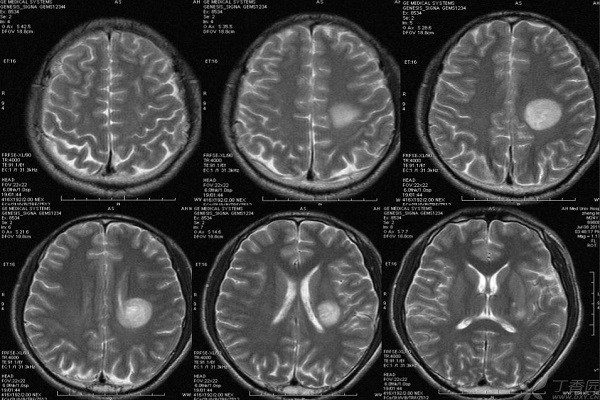

【腦白質脫髓鞘】

腦白質脫髓鞘,就是指已經發育成熟的正常髓磷脂被破壞,即腦白質脫髓鞘疾病。它主要包括多發硬化、進行性多灶性腦白質病、急性散發性腦脊髓炎、亞急性硬化性全腦炎、橋腦中央髓鞘溶解癥、胼胝體變性、皮層下動脈硬化性腦病和同心圓硬化等。